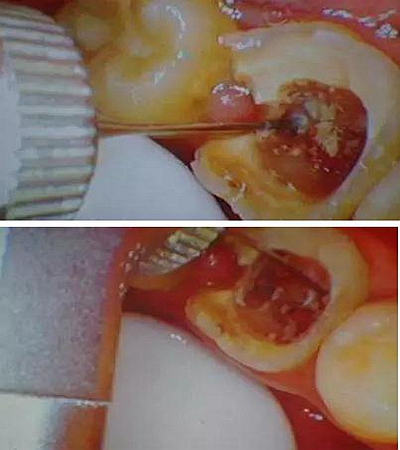

因為腐質(zhì)比較多用剔挖器處理:

剔挖器進一步處理后見到底穿部位:根管挖匙派上用場,穿孔部位有少許膿液。